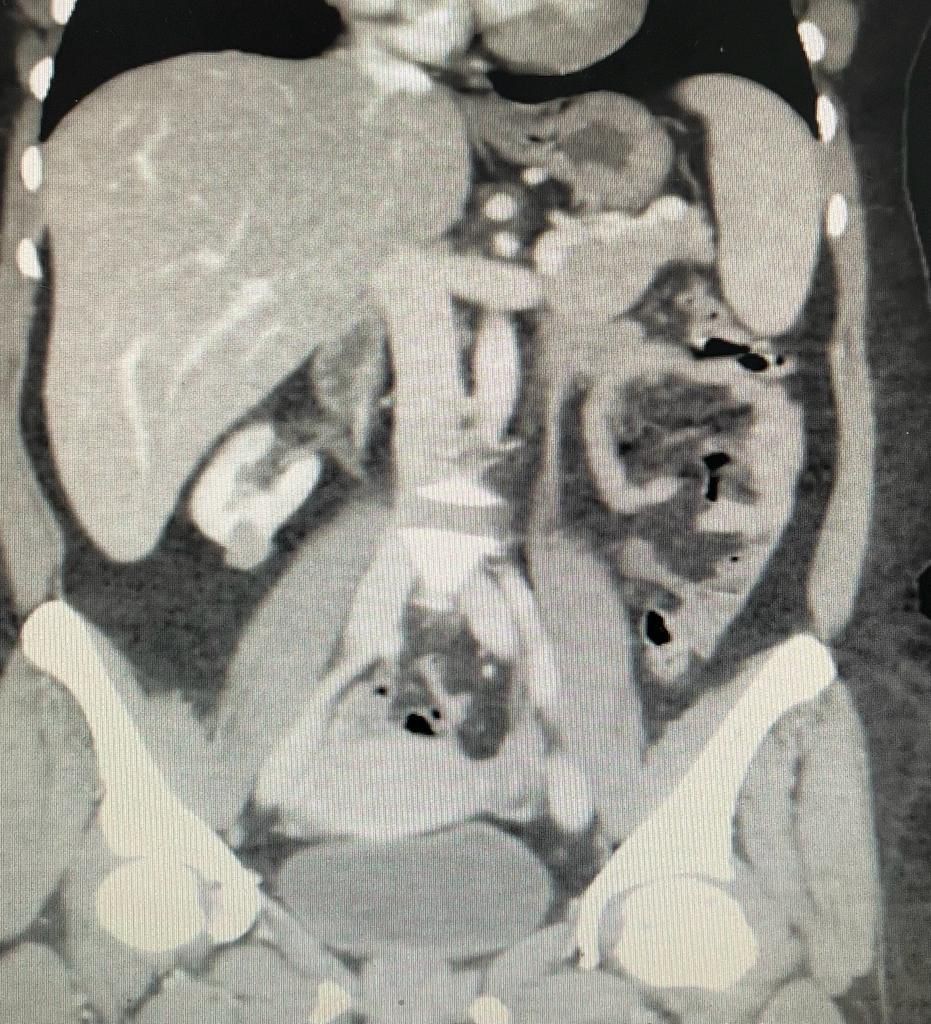

وتم عمل الفحوصات والأشعات الأولية، واتضح وجود ورم في الكلية اليمنى للمريضة، فتم إجراء عملية بالمنظار تم خلالها استئصال الورم كاملاً مع استئصال جزء من الكلية ( الحد الآمن ) للورم وإعادة اصلاح الكلية ، في إجراء طبي ناجح، وبعد تقديم الرعاية الصحية اللازمة للمريضة تماثلت للشفاء وهي بصحة جيدة ولله الحمد.